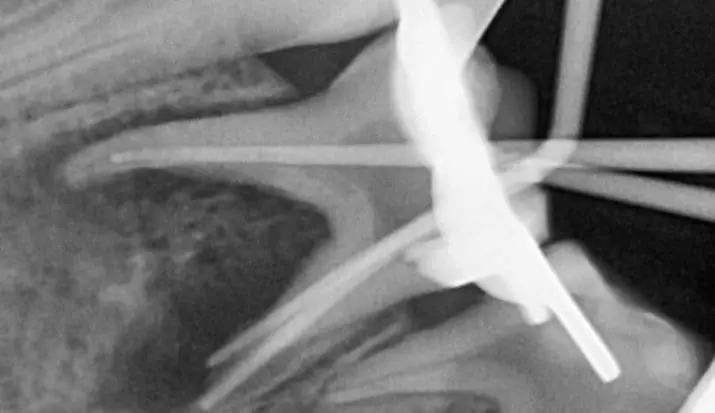

Тимчасові зуби мають ряд особливостей, які не характерні для постійних. Саме тому дитяча ендодонтія відрізняється від дорослої і просте перенесення технік роботи з постійних зубів на тимчасові призводить до серйозних помилок і ускладнень. Наш курс створений для того, аби лікарі впевнено орієнтувались у діагностиці, лікувальній тактиці та її реалізації. Для цього ми розглядаємо питання особливостей анатомії тимчасових зубів, перебігу патології ендодонту тимчасових зубів. В курсі детально подані протоколи лікування, інструменти та матеріали, які використовують для терапії пульпи та кореневих каналів тимчасових зубів. Також дані чіткі критерії визначення терапевтичної чи хірургічної тактики лікування тимчасових зубів. А відеодемонстрація на фантомі та клінічному прийомі дозволить втілити опрацьований матеріал в практику максимально ефективно.